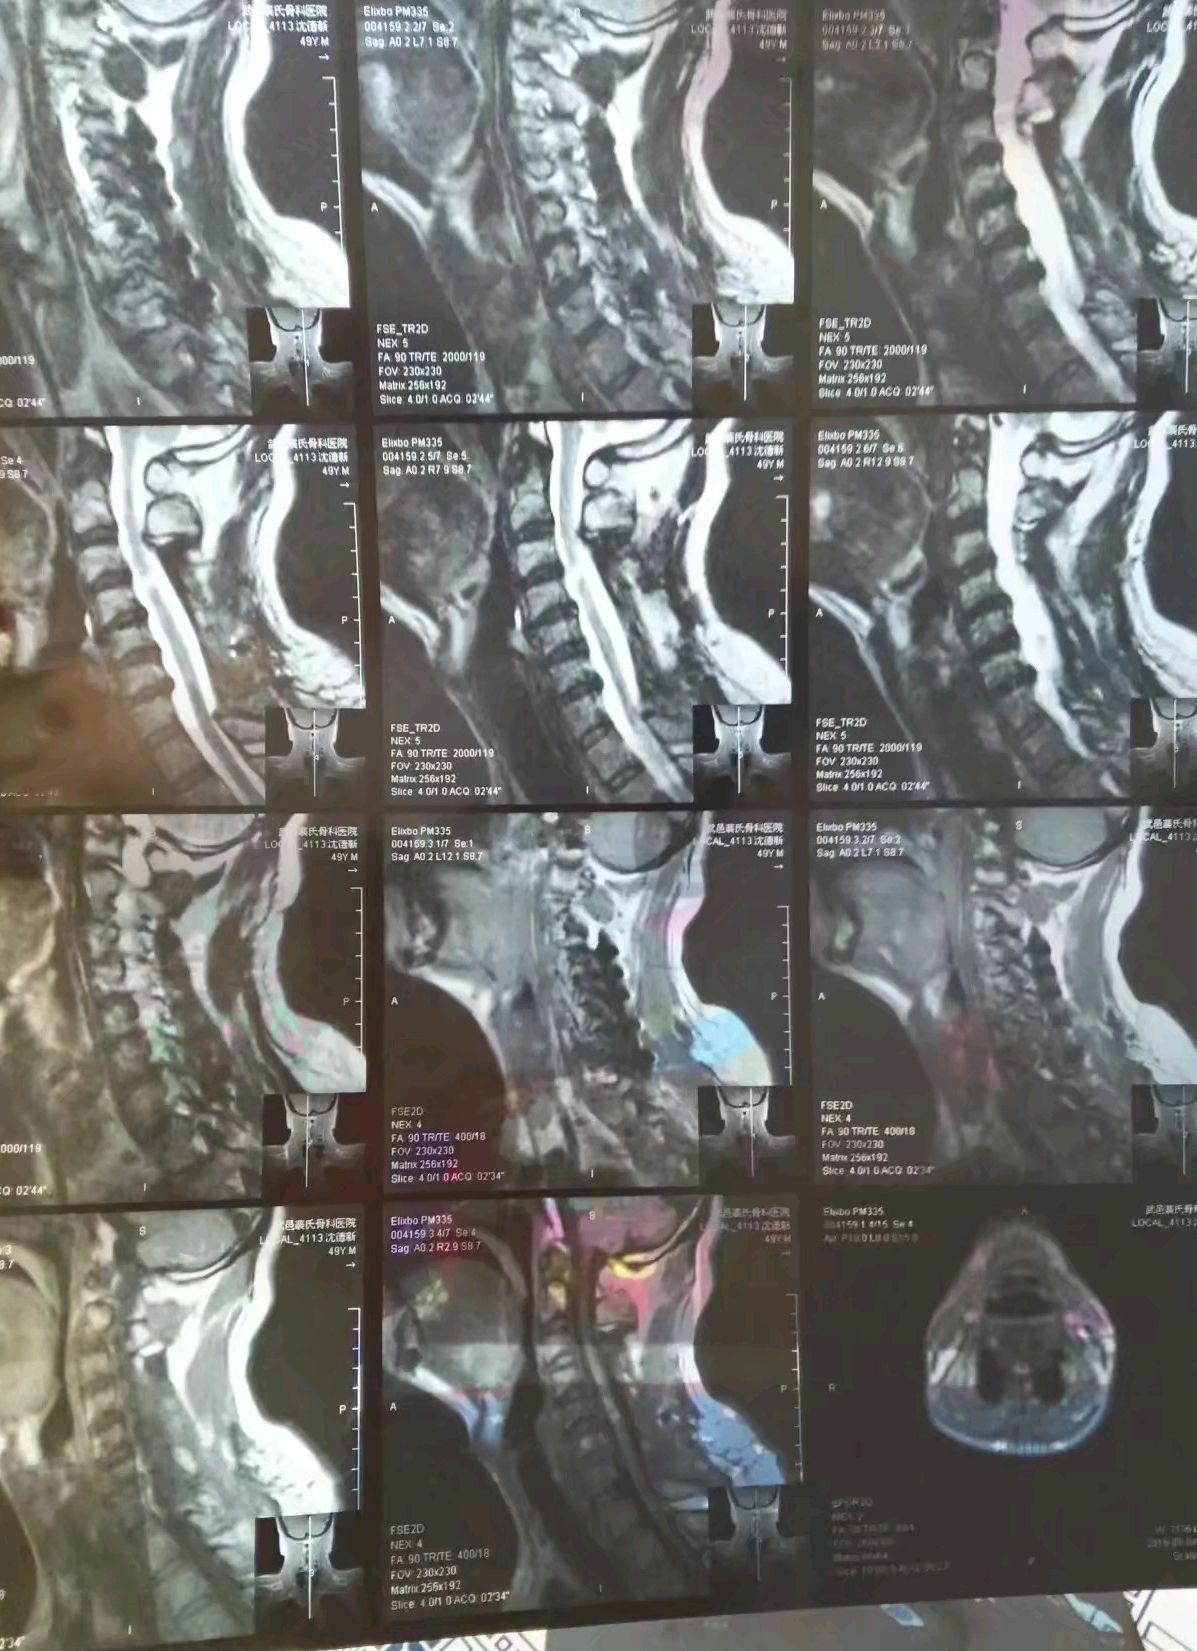

2018年一例严重的颈椎外伤

图片尺寸1080x1920